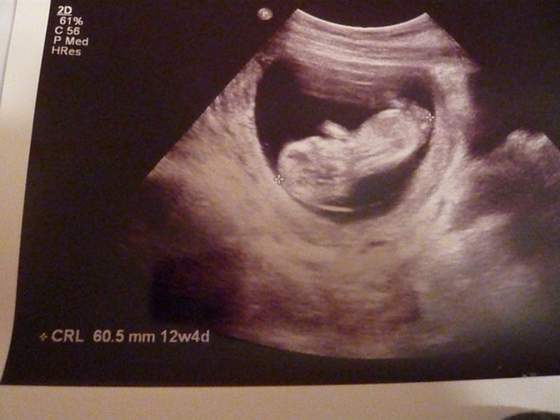

dlatego musze zmienic ginusia po raz 2 :-) wstawiam Moja Kluseczke

i opis badania tak dla waszego porównania:-)